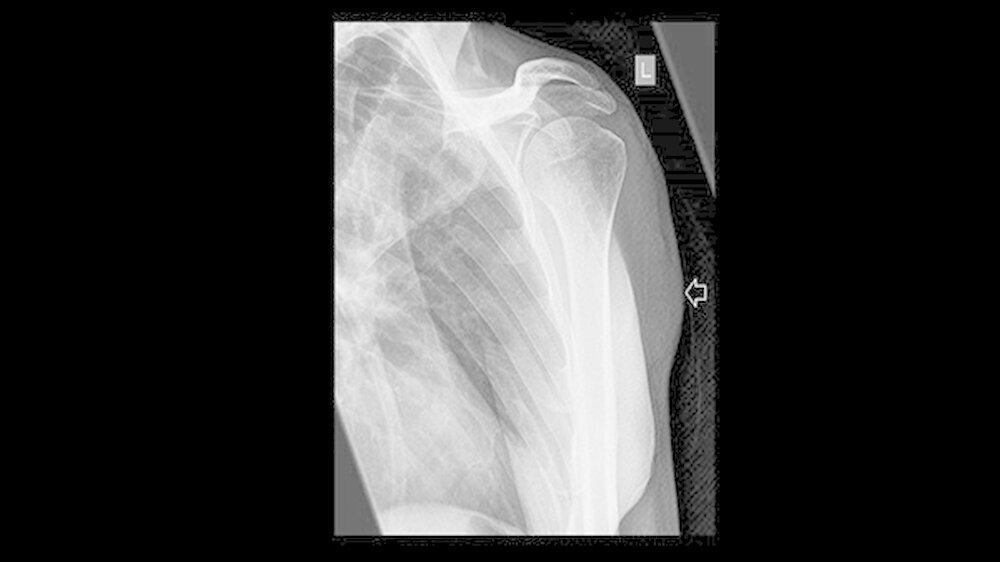

Ein Jahr nach der Exzision des Primärtumors, der begleitenden Radiatio sowie dem mikrochirurgischenAufbau des Unterkieferdefekts stellte sich der Patient erneut vor, um einen Termin zur Entfernung des Osteosynthesematerials zu vereinbaren. Bei dieser Untersuchung bemerkten die Chirurgen eine erhebliche Raumforderung am linken Oberarm, die nach Angaben des Patienten sehr schnellem Wachstum.

Weder das Röntgenbild noch die weitere Untersuchung mit magnetresonanztomografischer Bildgebung gaben eindeutigen Aufschluss. Daraufhin wurde eine Biopsie veranlasst, die die Verdachtsdiagnose einer Metastase des oralen Plattenepithelkarzinoms histologisch bestätigte.

Die Metastase wurde mittels Radiatio behandelt. Da Patienten mit Plattenepithelkarzinom und regionalen Lymphknotenmetastasen eine höhere Wahrscheinlichkeit haben, Fernmetastasen zu entwickeln und sich – nicht zuletzt wie dieser Patientenfall zeigt – auch entfernte Metastasen über die Blutwege bilden können, empfiehlt die DGMKG eine systematische Tumornachsorge mittels bildgebender Verfahren durchzuführen.